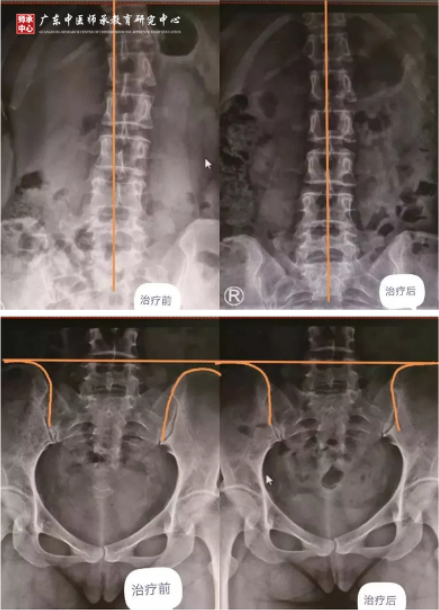

邹女士,37岁,腰痛,仰卧也痛,侧卧还是痛,左下肢放射痛,无法久坐,行走困难,家人扶着至胥主任处就医,腰椎侧歪,骨盆高低旋转所引起。

2019年7月26日——2019年11月16日,通过骨筋脉三联疗法治疗,诸痛消失,能够自己独立行走。

三联疗法治疗前后对比